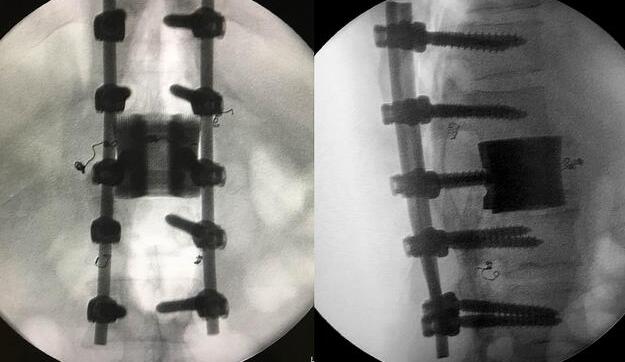

增材制造的椎體/腰間盤一體化植入物

利用3D打印技術(shù)生產(chǎn)出來的人工椎體是完全按照患者的解剖結(jié)構(gòu)完成脊椎結(jié)構(gòu)重建及固定的, 裝上一枚精準(zhǔn)的、個(gè)性化的人工脊椎,患者康復(fù)后完全可以正常地生活和工作。過去這種手術(shù)常常是使用鈦網(wǎng)內(nèi)填入自體或異體碎骨作為椎體間支撐材料,但鈦網(wǎng)一旦移位壓迫脊髓,患者就會(huì)有癱瘓的風(fēng)險(xiǎn)。這次手術(shù)中的脊椎植入物內(nèi)部具有經(jīng)過力學(xué)優(yōu)化設(shè)計(jì)的晶格結(jié)構(gòu),比傳統(tǒng)鈦網(wǎng)具有更強(qiáng)的承重力,金屬3D打印可以直接制造出這樣的復(fù)雜結(jié)構(gòu)。

***終在經(jīng)歷近八個(gè)小時(shí)后,病人的家屬終于等到了好消息:人工椎體/椎間盤一體化金屬植入物成功植入,手術(shù)順利。由于病人術(shù)中出血量小,生命體征平穩(wěn),他不用進(jìn)入ICU觀察,直接回到了普通病房。 現(xiàn)在我們都很高興,成功做出了世界首例人工椎體/椎間盤一體化金屬植入物,病人今后可以與常人一樣工作和生活。鄭明輝醫(yī)生說。